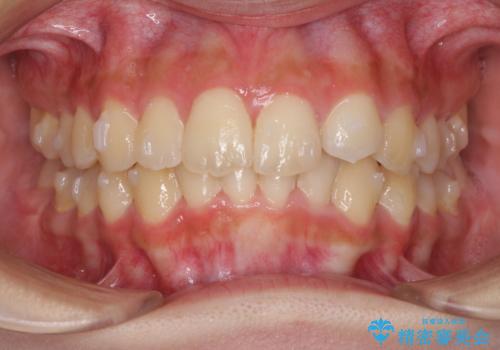

前歯のガタガタを目立たない装置でなおしたい インビザラインによる目立たない矯正

- 目立たない装置でガタガタをきれいにしたいとのご希望で来院されました。

インビザラインで矯正することとなりました。

左上の前から2番目の歯が通常とは異なる形態をしており、左右対称にすることはできませんでしたが、インビザラインで周りに気づかれることなく矯正治療をおえることができ、満足していただけました。